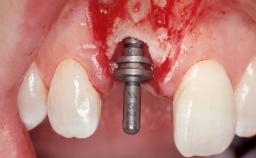

A 33-year-old female patient presented with an upper left central incisor that required extraction after a failed endodontic therapy. The tooth had been traumatized when the patient was a teenager and had undergone several endodontic treatments, including two apicectomy procedures. The patient was in good health and did not smoke. Clinical examination showed that the patient had a high lip line. In full smile, the gingival margins of the upper teeth were visible to the first molars. The gingival margins of central incisors 11 and 21 were only just showing. Examination of tooth 21 confirmed that the tooth was mobile and had hypererupted by 1 mm.

Soft Tissue Grafting Simultaneous

Placement Protocol Immediate implant placement

Socket Integrity Damage to one or more bone walls

Bone Volume Damage to one or more socket walls

Bone Augmentation Horizontal|Simultaneous

Augmentation Materials Xenogenous|Membrane